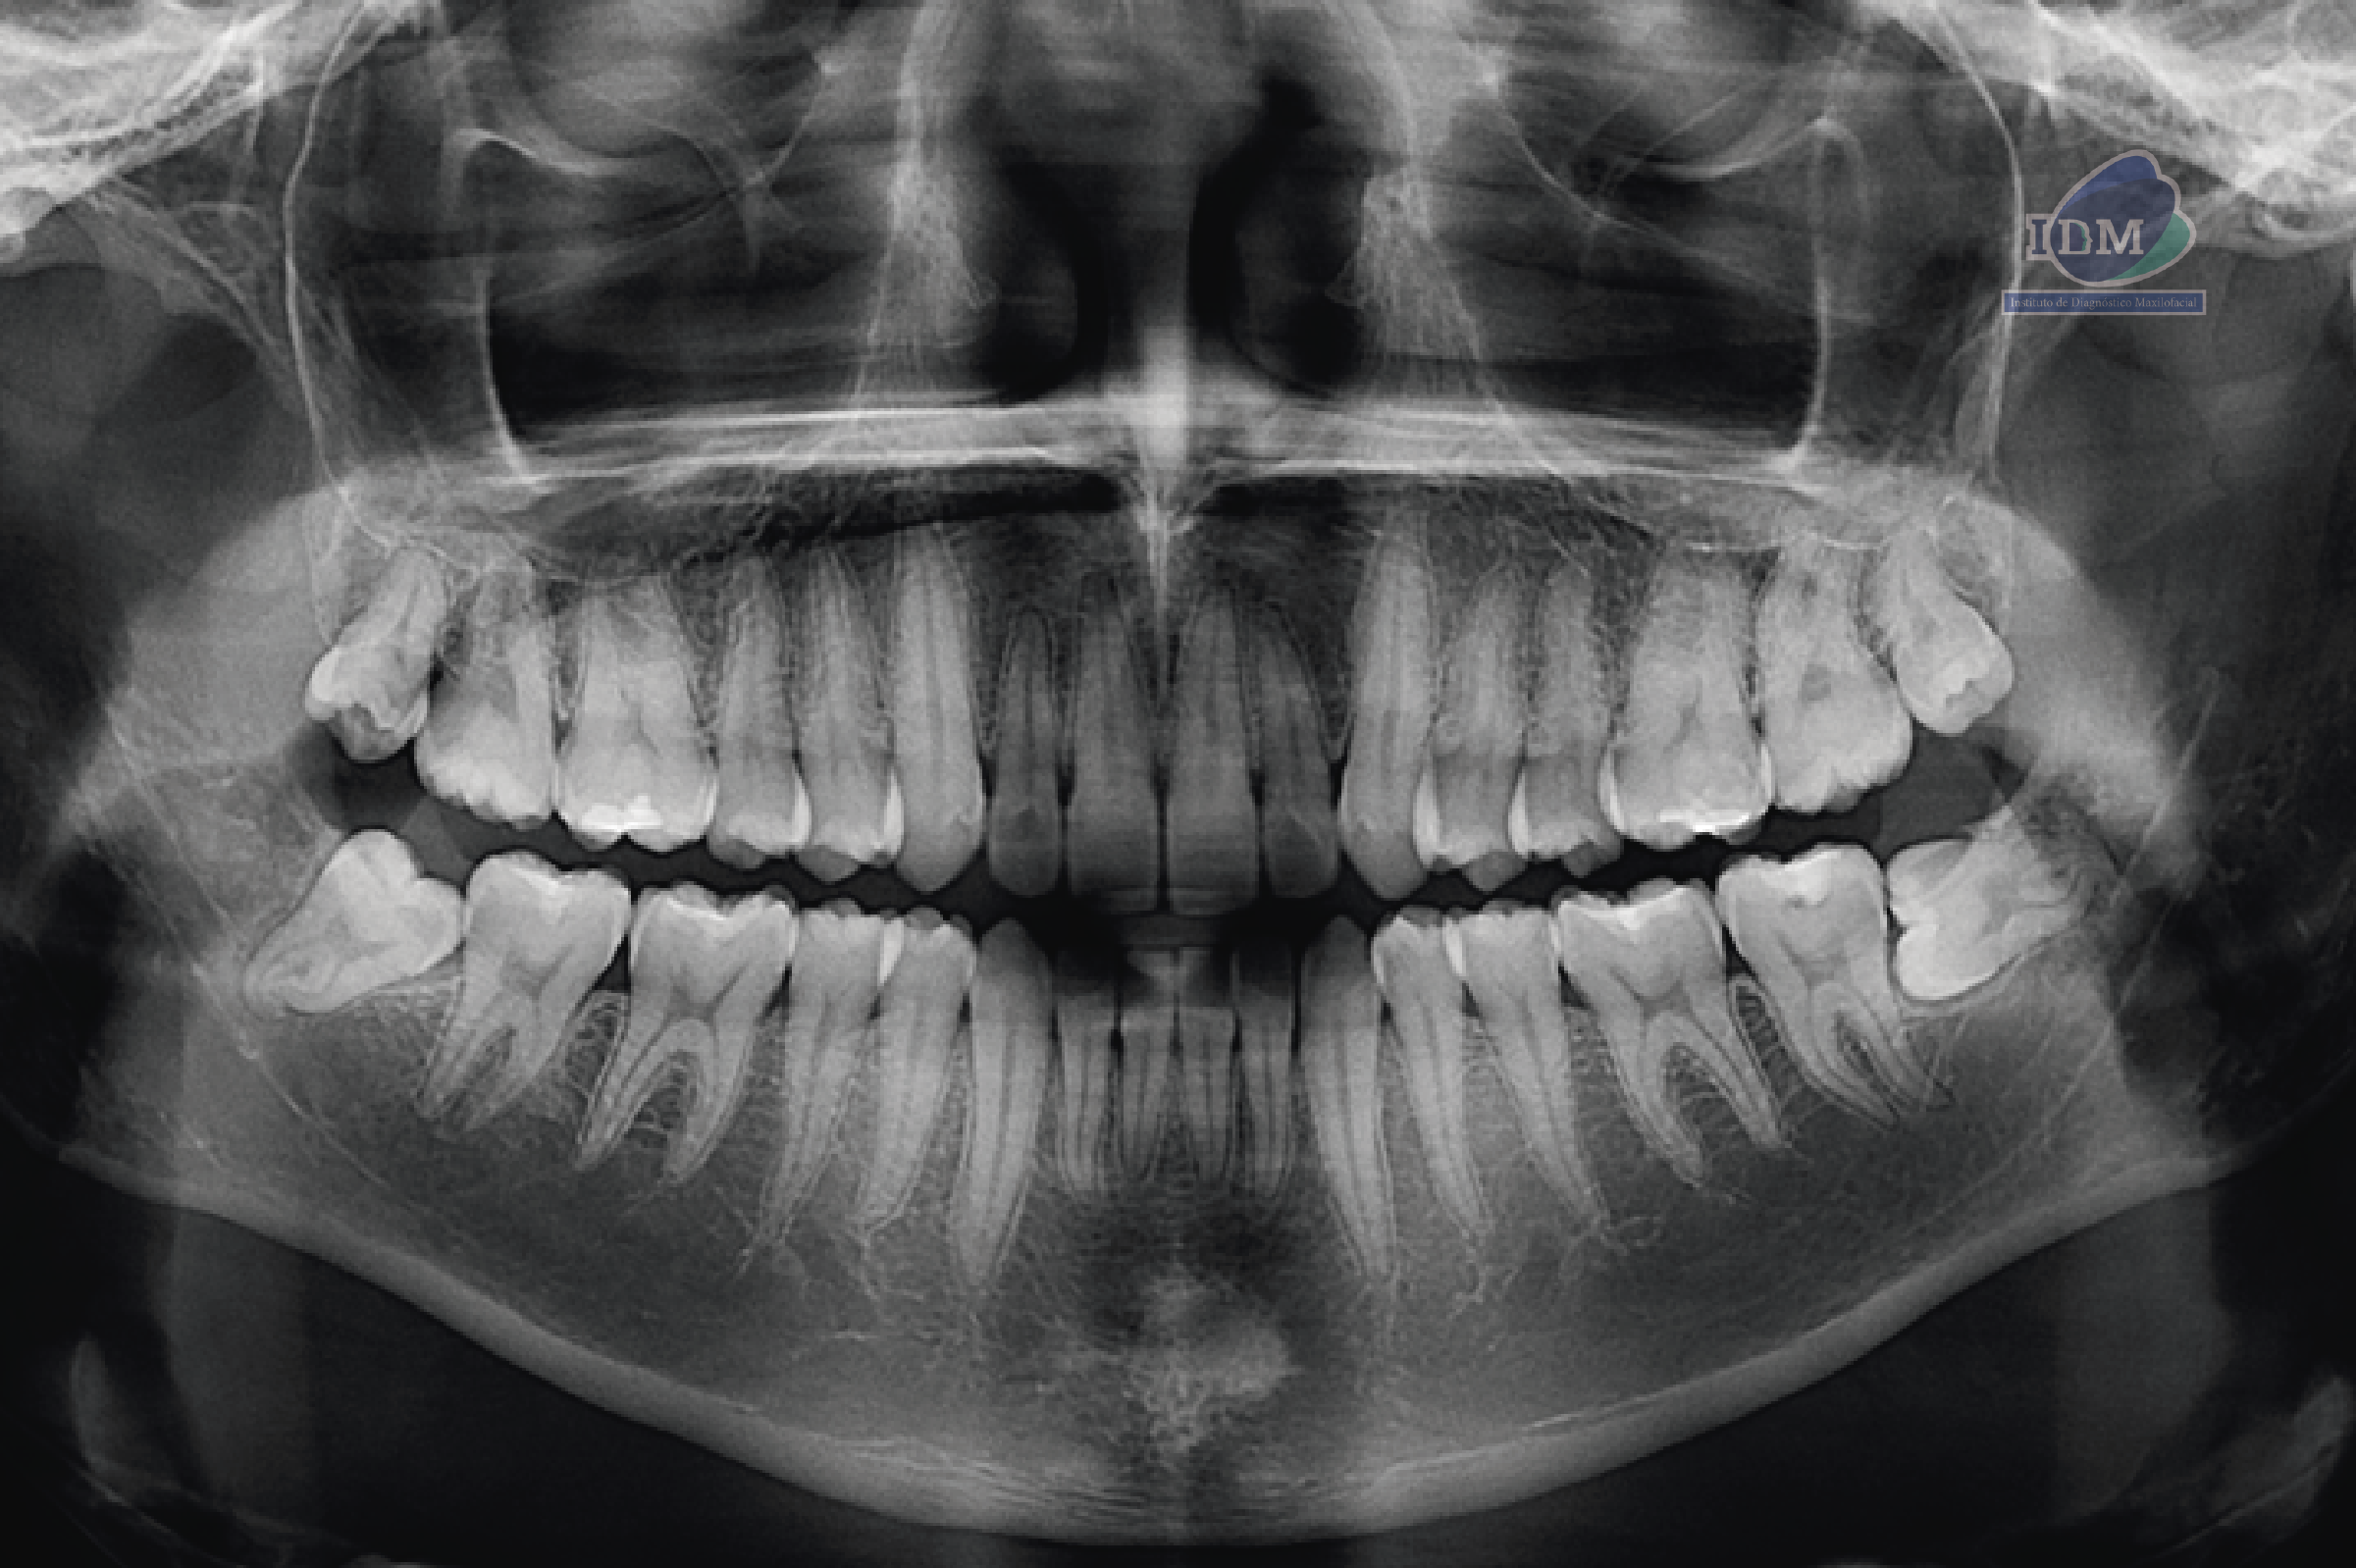

En la radiografía panorámica (Figura 1), se aprecia imagen radiopaca proyectada sobre sínfisis mandibular.

Radiografia Panorámica